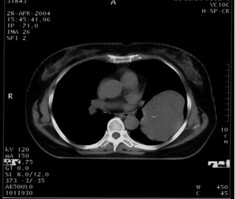

女,62岁。右大腿滑膜肉瘤,术后左下肺转移,9.5×7.5cm。CT引导下瘤内注射今又生,1×1012VP/次/周,共8次,结合60Gy放射照射。治疗后肿瘤缩小48%,CT示瘤内低密度区占50%以上,即肿瘤大部分坏死。

治疗前